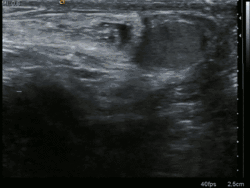

En la mayoría de los casos, se puede hacer un diagnóstico de hernia inguinal o femoral con base en la historia clínica y el examen físico de la ingle, sin necesidad de realizar más estudios. Aunque los datos son limitados, un estudio informó de una sensibilidad del 75 % y una especificidad del 96 % para un diagnóstico de hernia inguinal en el examen físico realizado por cirujanos. El diagnóstico puede ser más difícil en mujeres y personas con obesidad, para quienes puede ser necesaria una evaluación diagnóstica adicional. Rara vez se requieren exámenes adicionales para confirmar el diagnóstico. En ciertos casos, un ultrasonido o un TAC se justifican, en particular para descartar un hidrocele. [5,7] El ultrasonido aumenta la sensibilidad para detectar una hernia oculta del 80 % solo y con el examen físico al 96 %.[9]